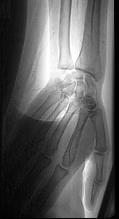

- 单项选择题43岁女性患者,突发左手疼痛伴多个指头麻木就诊, 行左上肢动脉照影,示左侧桡动脉广泛的充盈缺损, 结合临床考虑左侧桡动脉病变为 ( )